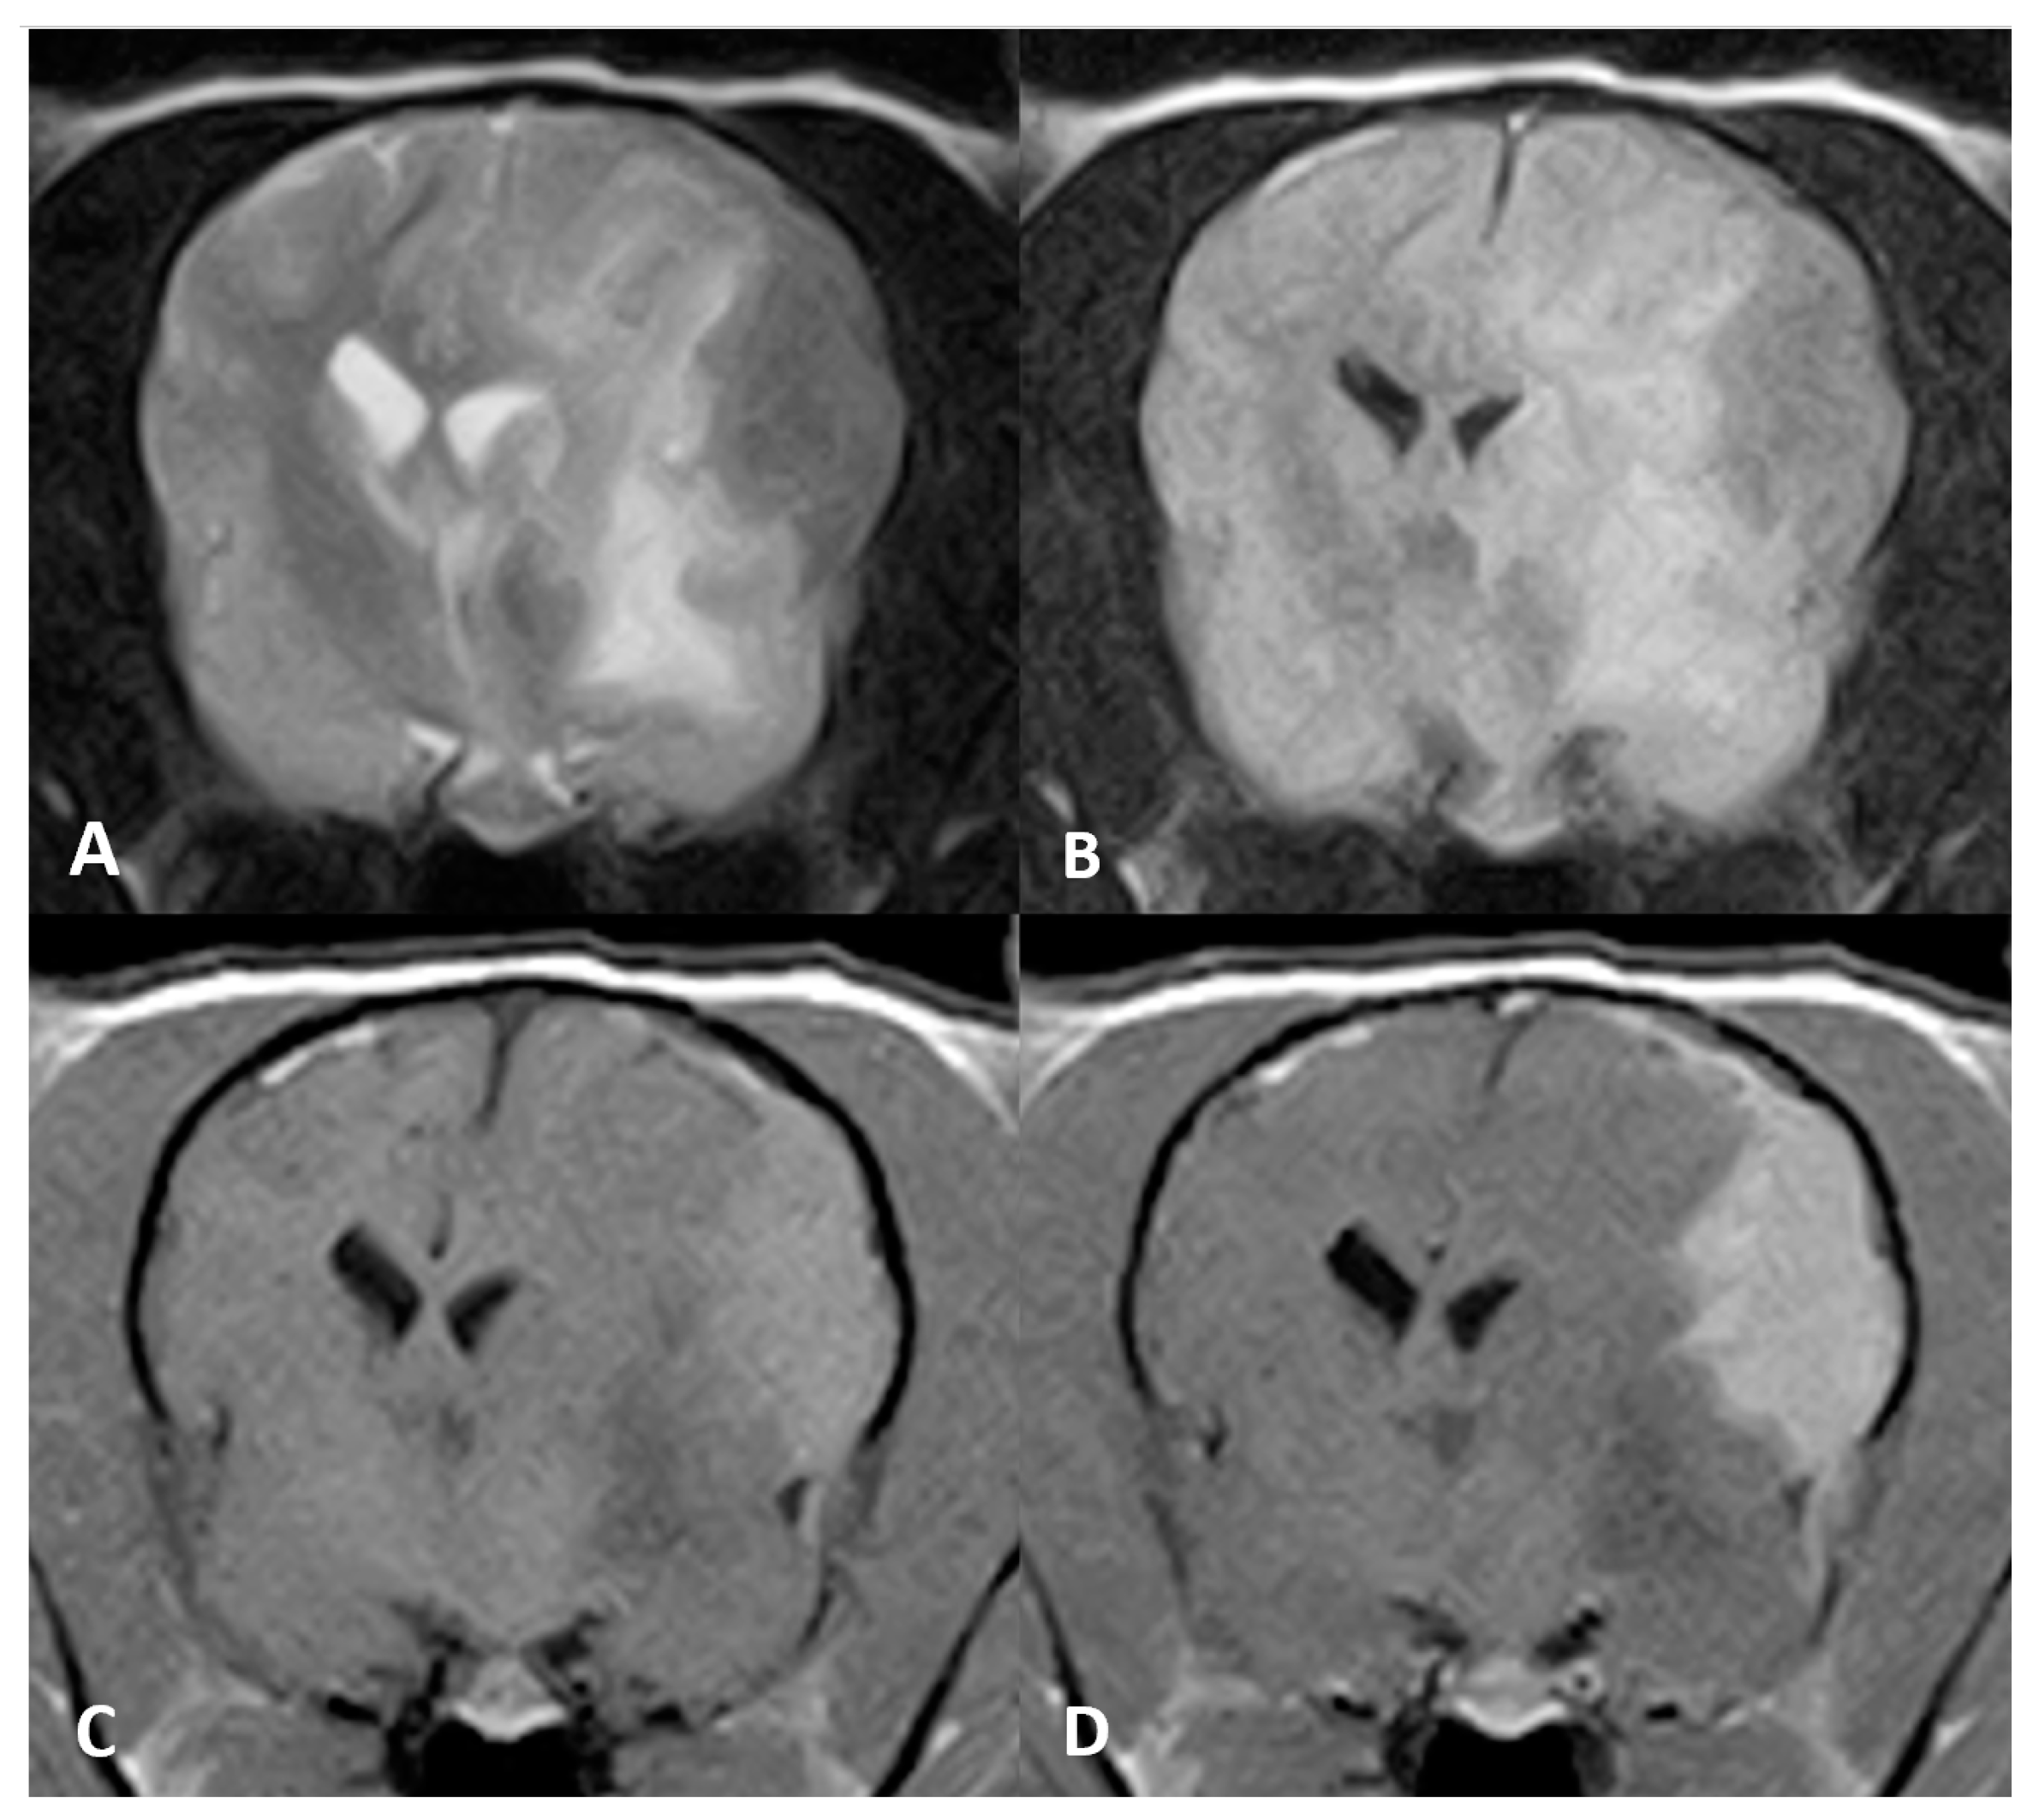

On brain MR imaging, a well-defined extra-axial mass was seen affecting the meninges covering the left hemisphere (both the parietal and temporal cortices) (see Figure 3). The mass was hypointense on T2w and FLAIR relative to grey matter and hyperintense on T1w precontrast with strong homogeneous contrast enhancement. Adjacent to the mass, T2w and FLAIR hyperintensities were evident, extending along the white matter tracts of the whole left cerebral hemisphere. The mass was causing severe mass effect with concurrent subfalcine brain herniation and mild foraminal herniation of the vermis cerebellum.

Figure 3. MR imaging of the brain of Case 3, transverse images at the level of the thalamus. An ovoid, plaquelike extra-axial mass is seen in the left parietal cortex. The mass was hypointense on (A) T2w and (B) FLAIR images. (C) Evident T1w hyperintense signal and (D) marked enhancement after contrast administration.